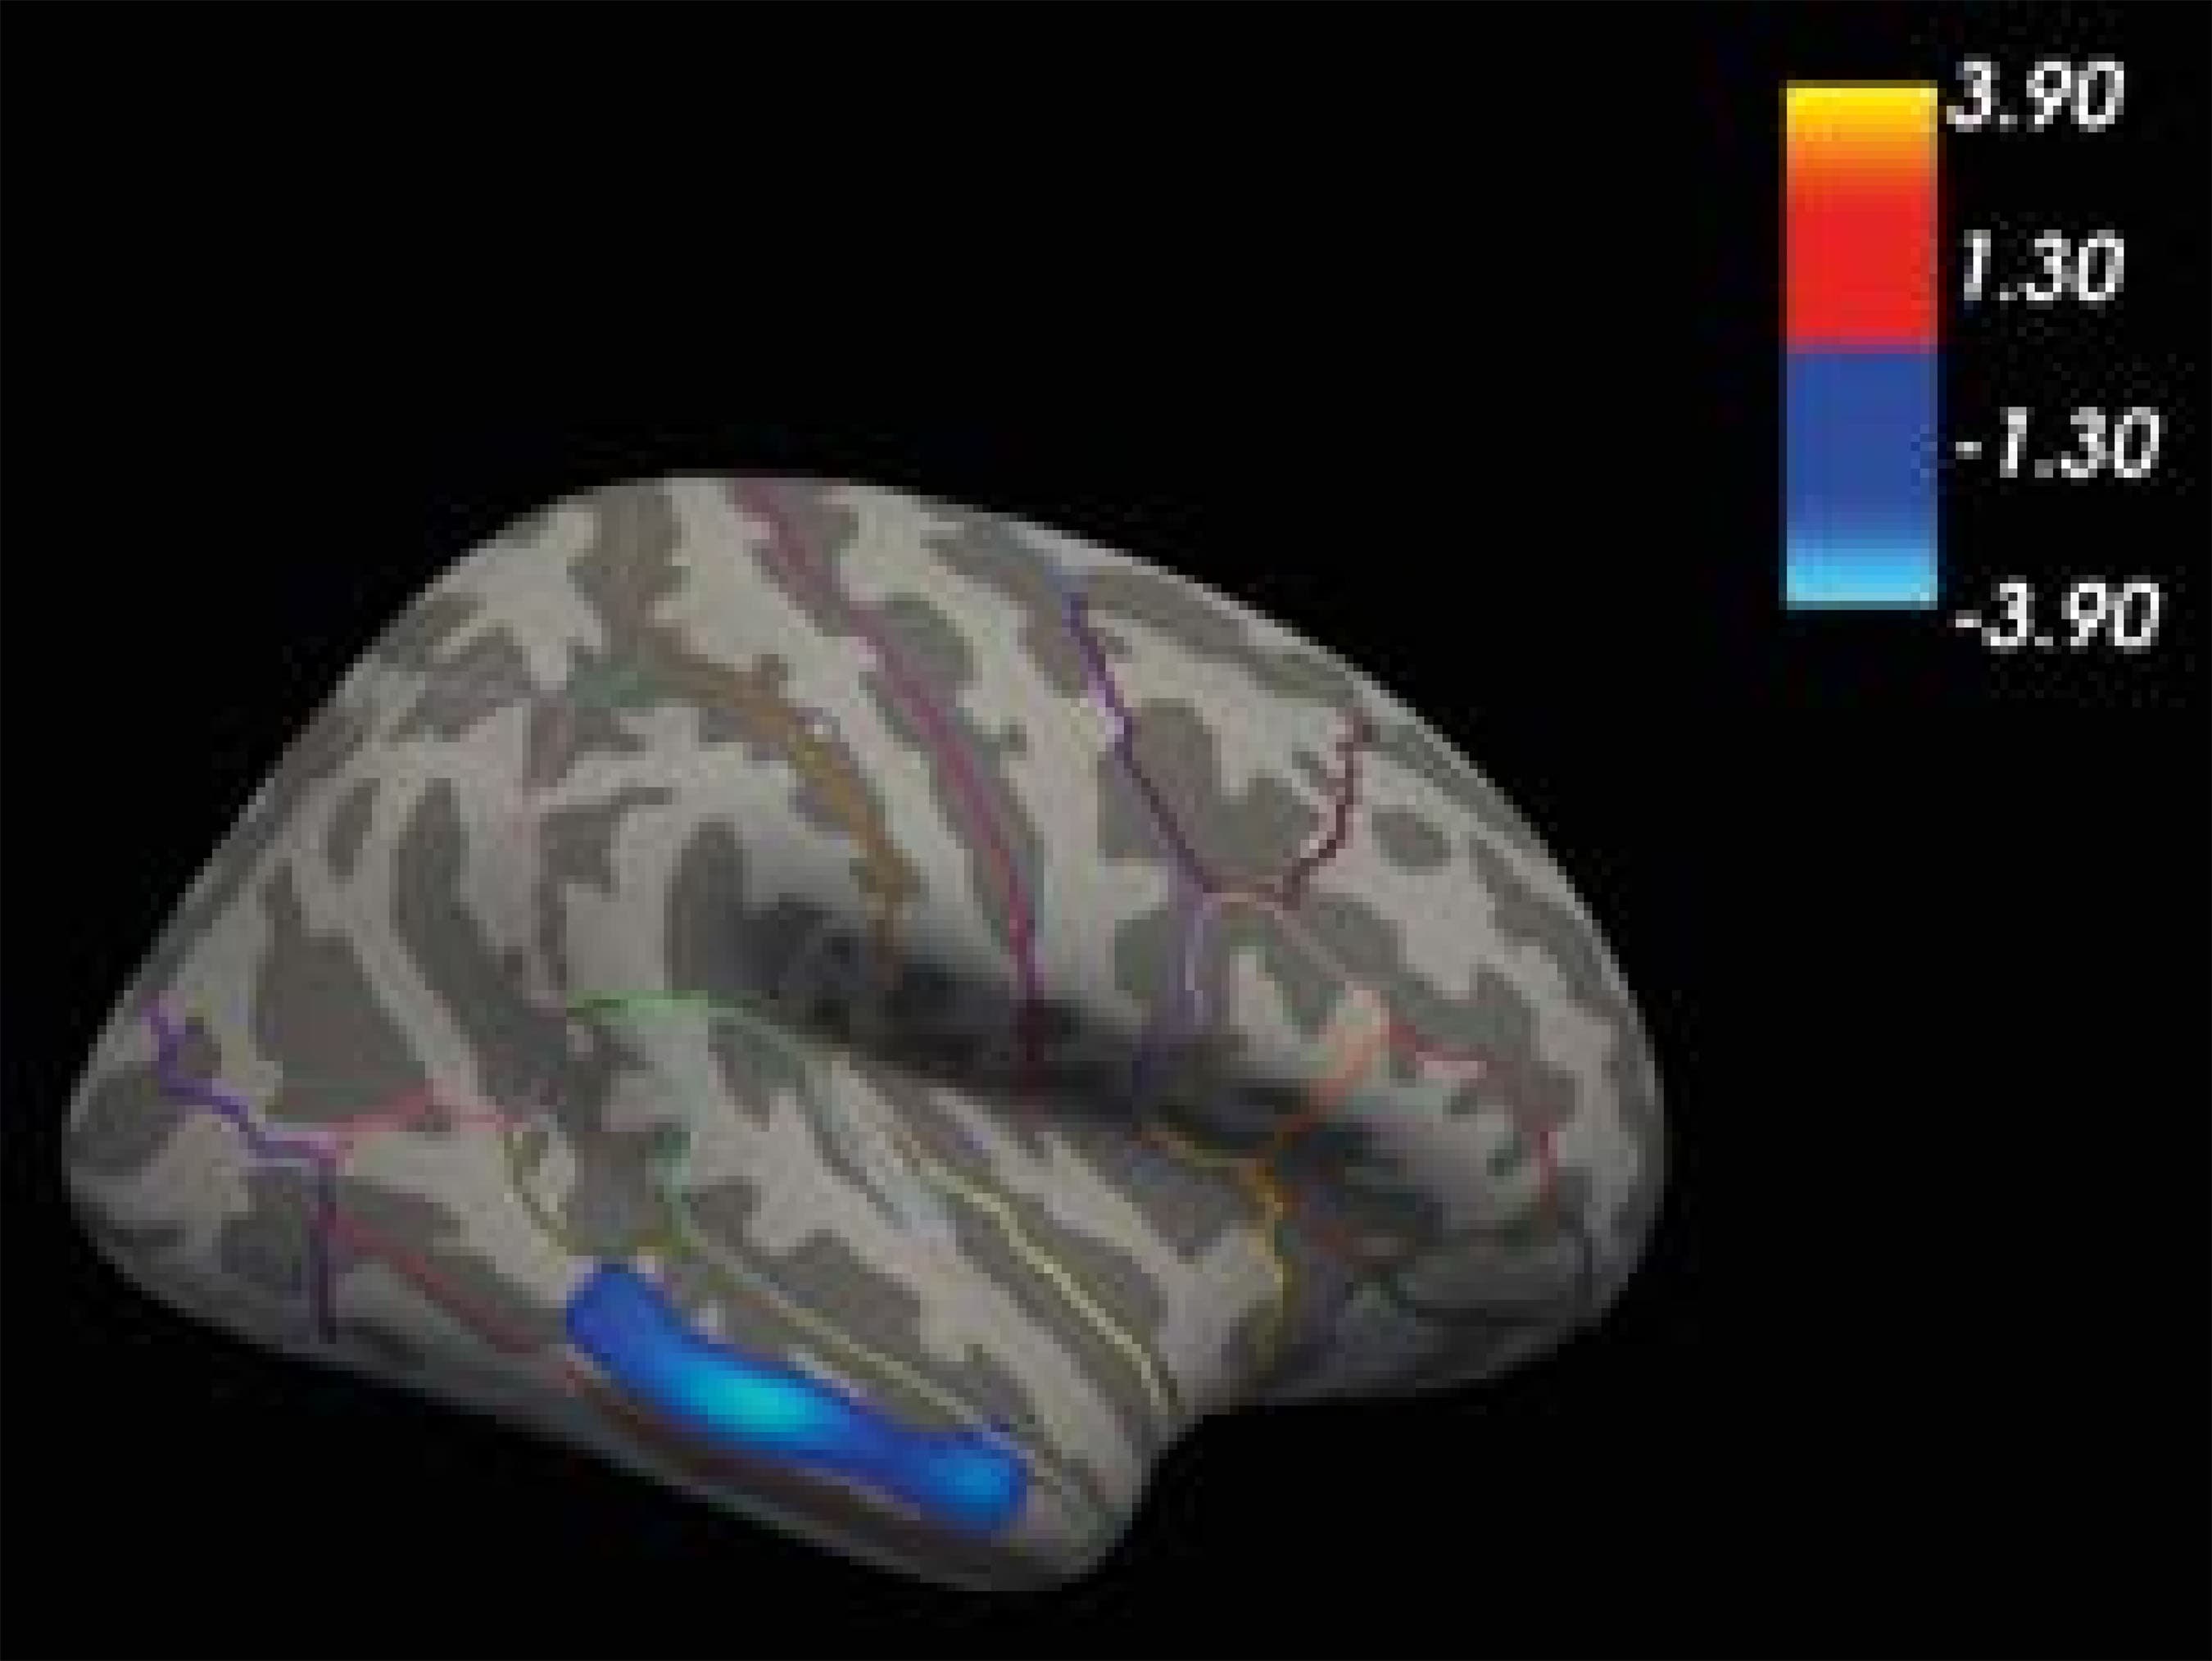

For our first aim, we analyzed the cortical features that differed significantly between the two groups using ANOVA. A significant increment in the cortical thickness of the right middle temporal cluster was found in the OG as compared to the CG (CG: M = 2.74, SD = 0.11; OG: M = 2.89, SD = 0.15; F(1, 47) = 14.25; p < .001, d=1.14), as shown in Table 2 and Figure 1.

Figure 1: Decreased Cortical Thickness in Control Group Versus Offender Group in One Cluster Comprising the Right Middle Temporal Gyrus. Background Brain Image Represents the Lateral View of the Right Hemisphere of the Inflated FreeSurfer Fsaverage Brain.